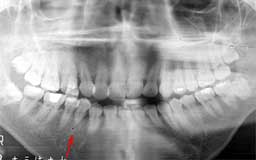

Nさん 初診時 51歳 女性

10年以上前からメインテナンスを受けていたということで、治療済みの歯や虫歯が多いもの の、歯周組織の状態は良好

Nさん 20年後 71歳

金属の被せが非常に目立ちますが、28本すべて健在は立派です